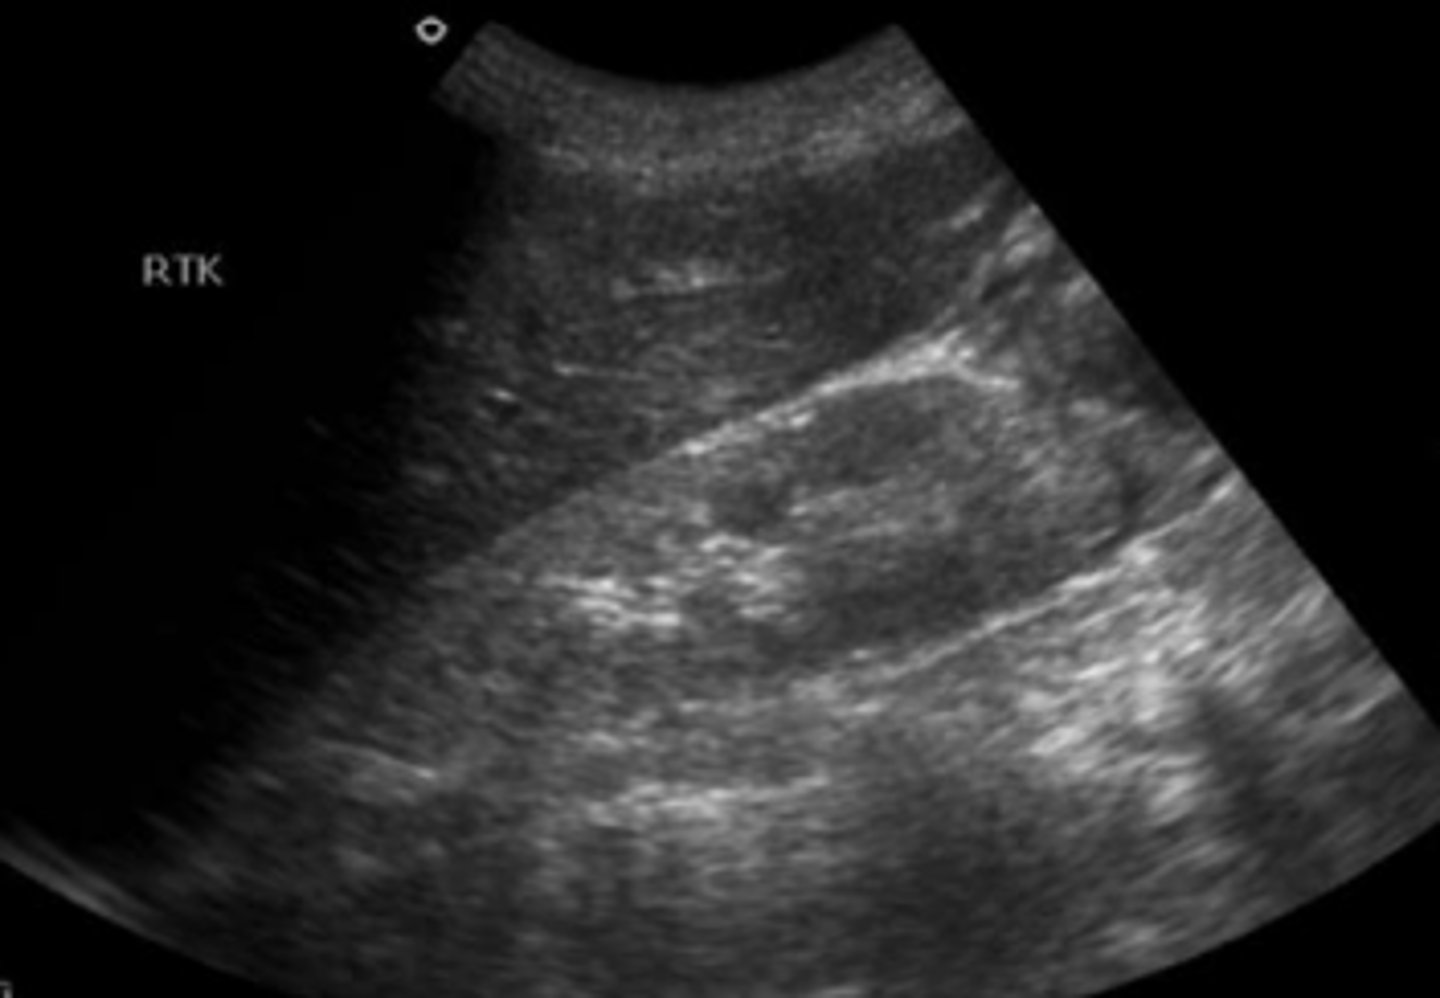

What is seen here?

medical renal disease--> increased cortical echogenicity

What is seen here?